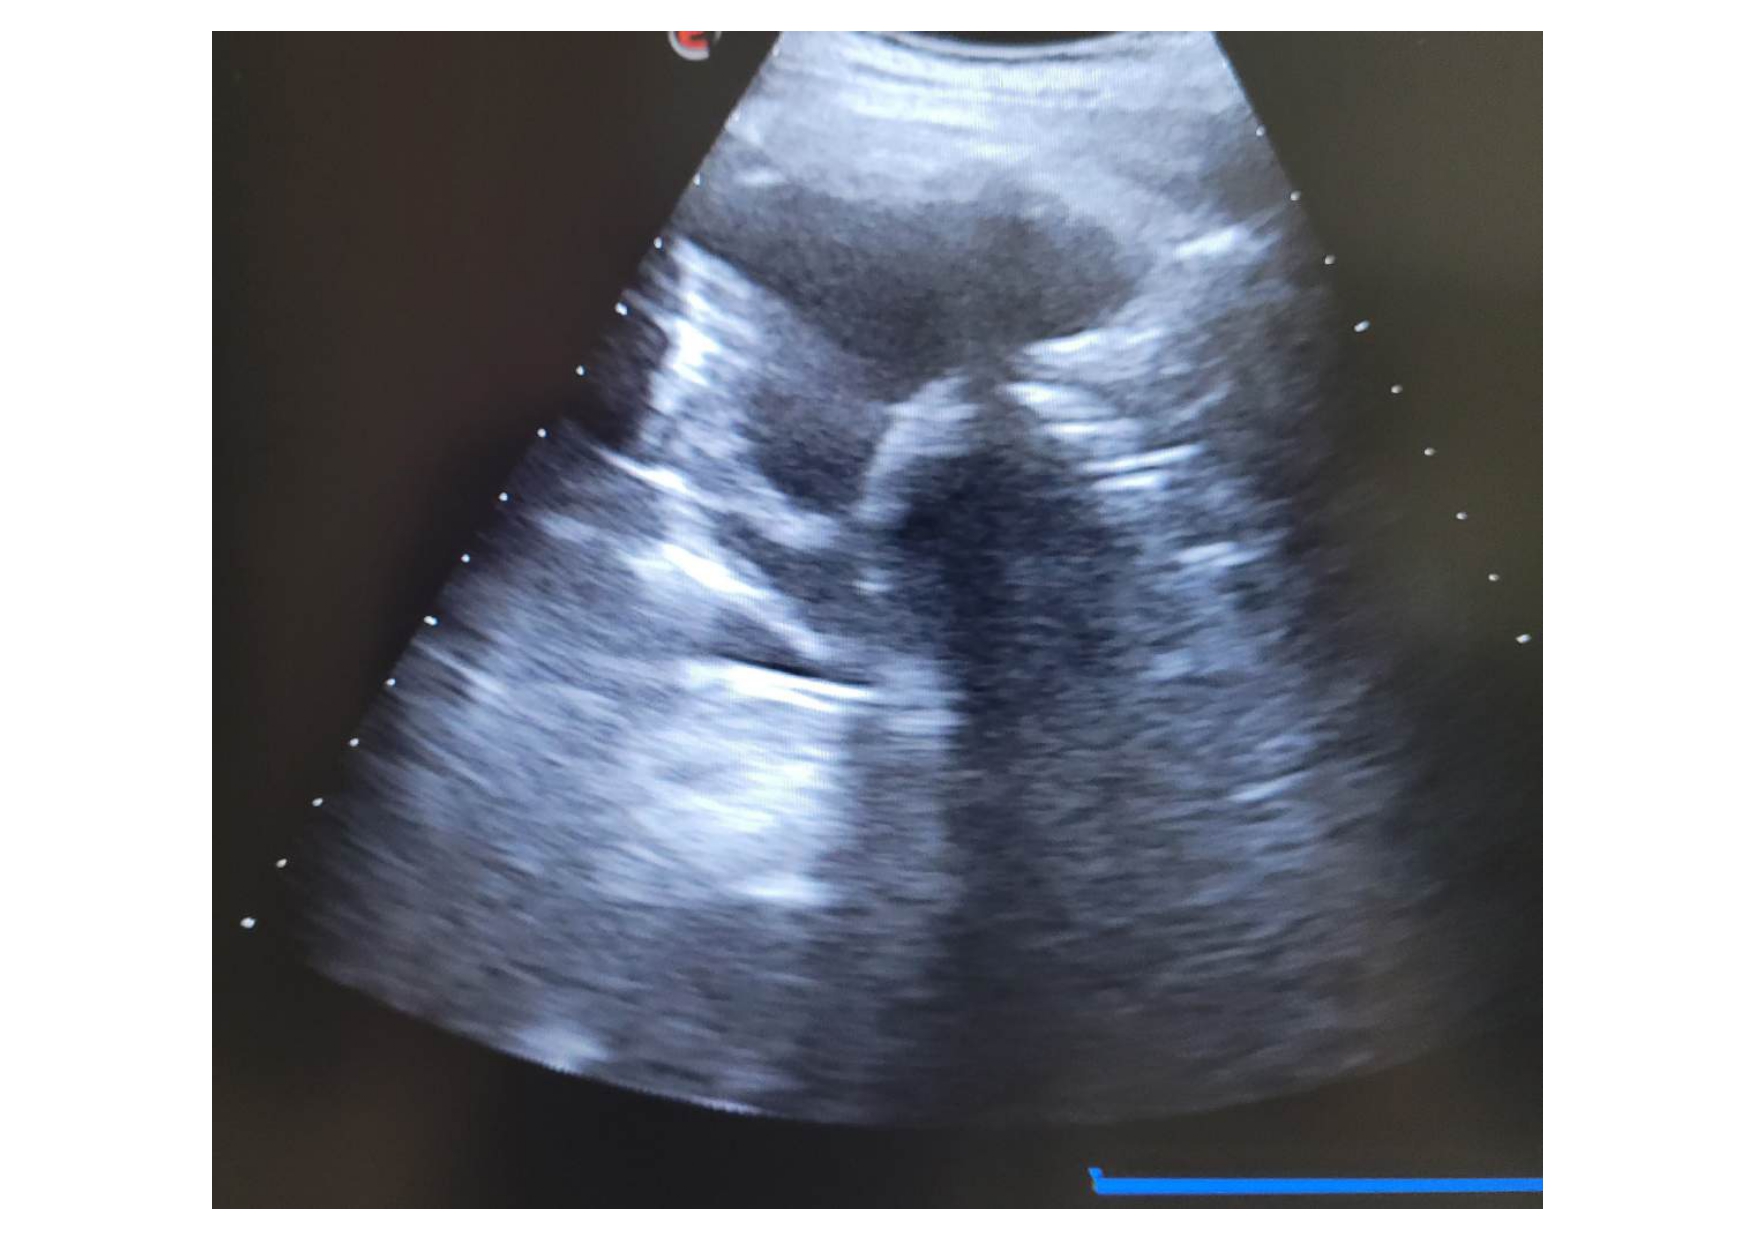

Se realiza una ecografía pulmonar, donde se observa un derrame pleural bilateral, de mayor cuantía a nivel izdo, con “signo de medusa” a ese nivel, con líneas B en áreas 6 y 12.